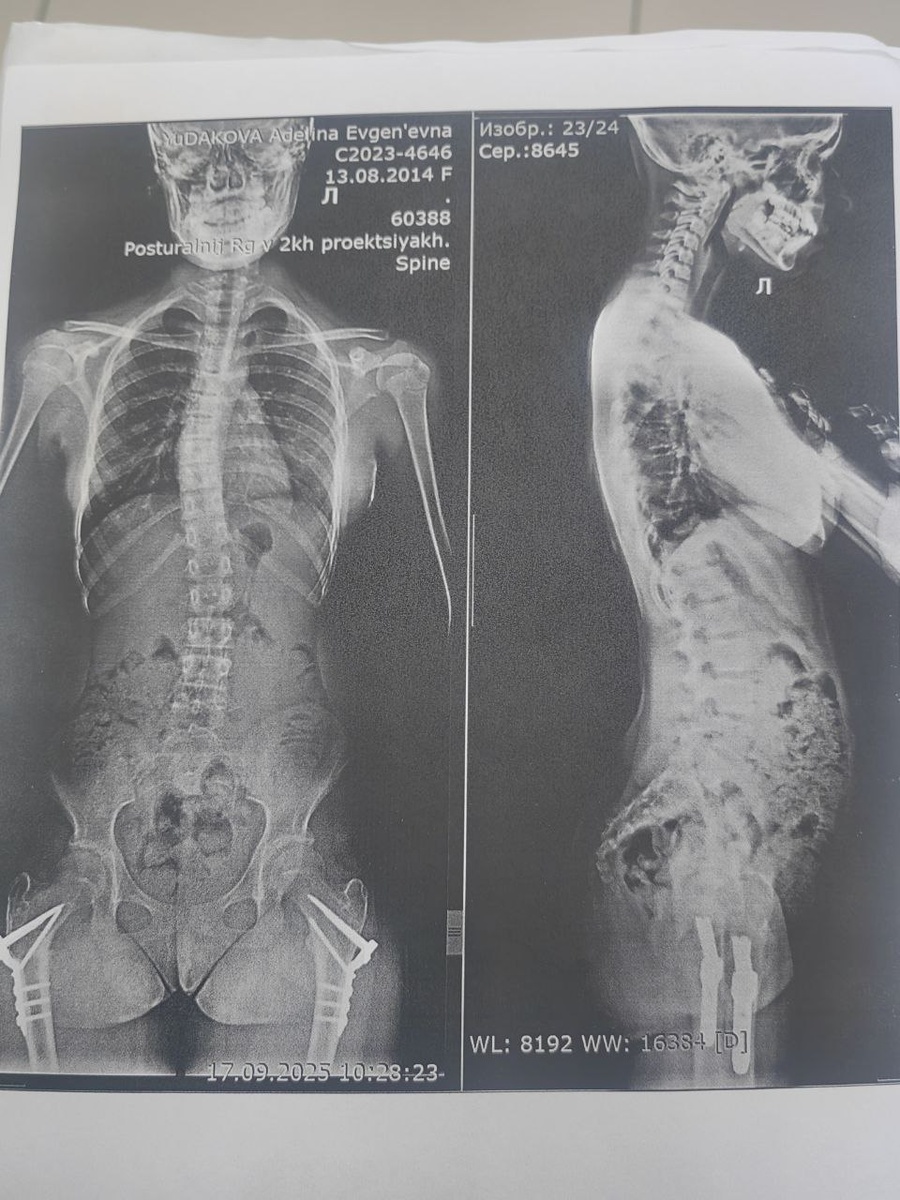

В понедельник я узнала о новом исследовании, которое называется не иначе как постуральный рентген позвоночника. То есть это сшивной рентгеновский снимок позвоночника, который выполняется в положении стоя. Оказывается, распознать истинный сколиоз можно только так. Выполнение из положения лёжа — это неинформативный способ диагностики. И вот, через десять минут после снимка я получила новый диагноз ребёнка.

Так выглядит снимок с постурального рентгена. Снимок позвоночника моей дочери

Вчера моя старшая дочь обзавелась новым диагнозом: идиопатический сколиоз 2 степени. Несколько дней мы разбирались с причинами и диагнозом, но наконец в этом вопросе поставлена точка. Вернее, запятая. Несколько лет Адель проходила лечение нижних конечностей с целью сохранения тазобедренных суставов. А именно деротационную корригирующую остеотомию нижних конечностей. То есть ей развернули суставы при помощи контролируемых переломов на 50 градусов. К сожалению, данные вмешательства привели к хромоте. Я сначала думала, что это связано с разницей в конечностях, но все врачи уверяли, что нет, и это всего лишь слабые рассечённые мышцы, которые нужно закачивать. Так и было, но в этот раз к походке добавилась спина, которая раскачивалась в противовес походке. На это и обратил внимание наш врач. В понедельник я узнала о новом исследовании, которое называется не иначе как постуральный рентген позвоночника. То есть это сшивной рентгеновский снимок позвоночника, который выполняется в положении сто